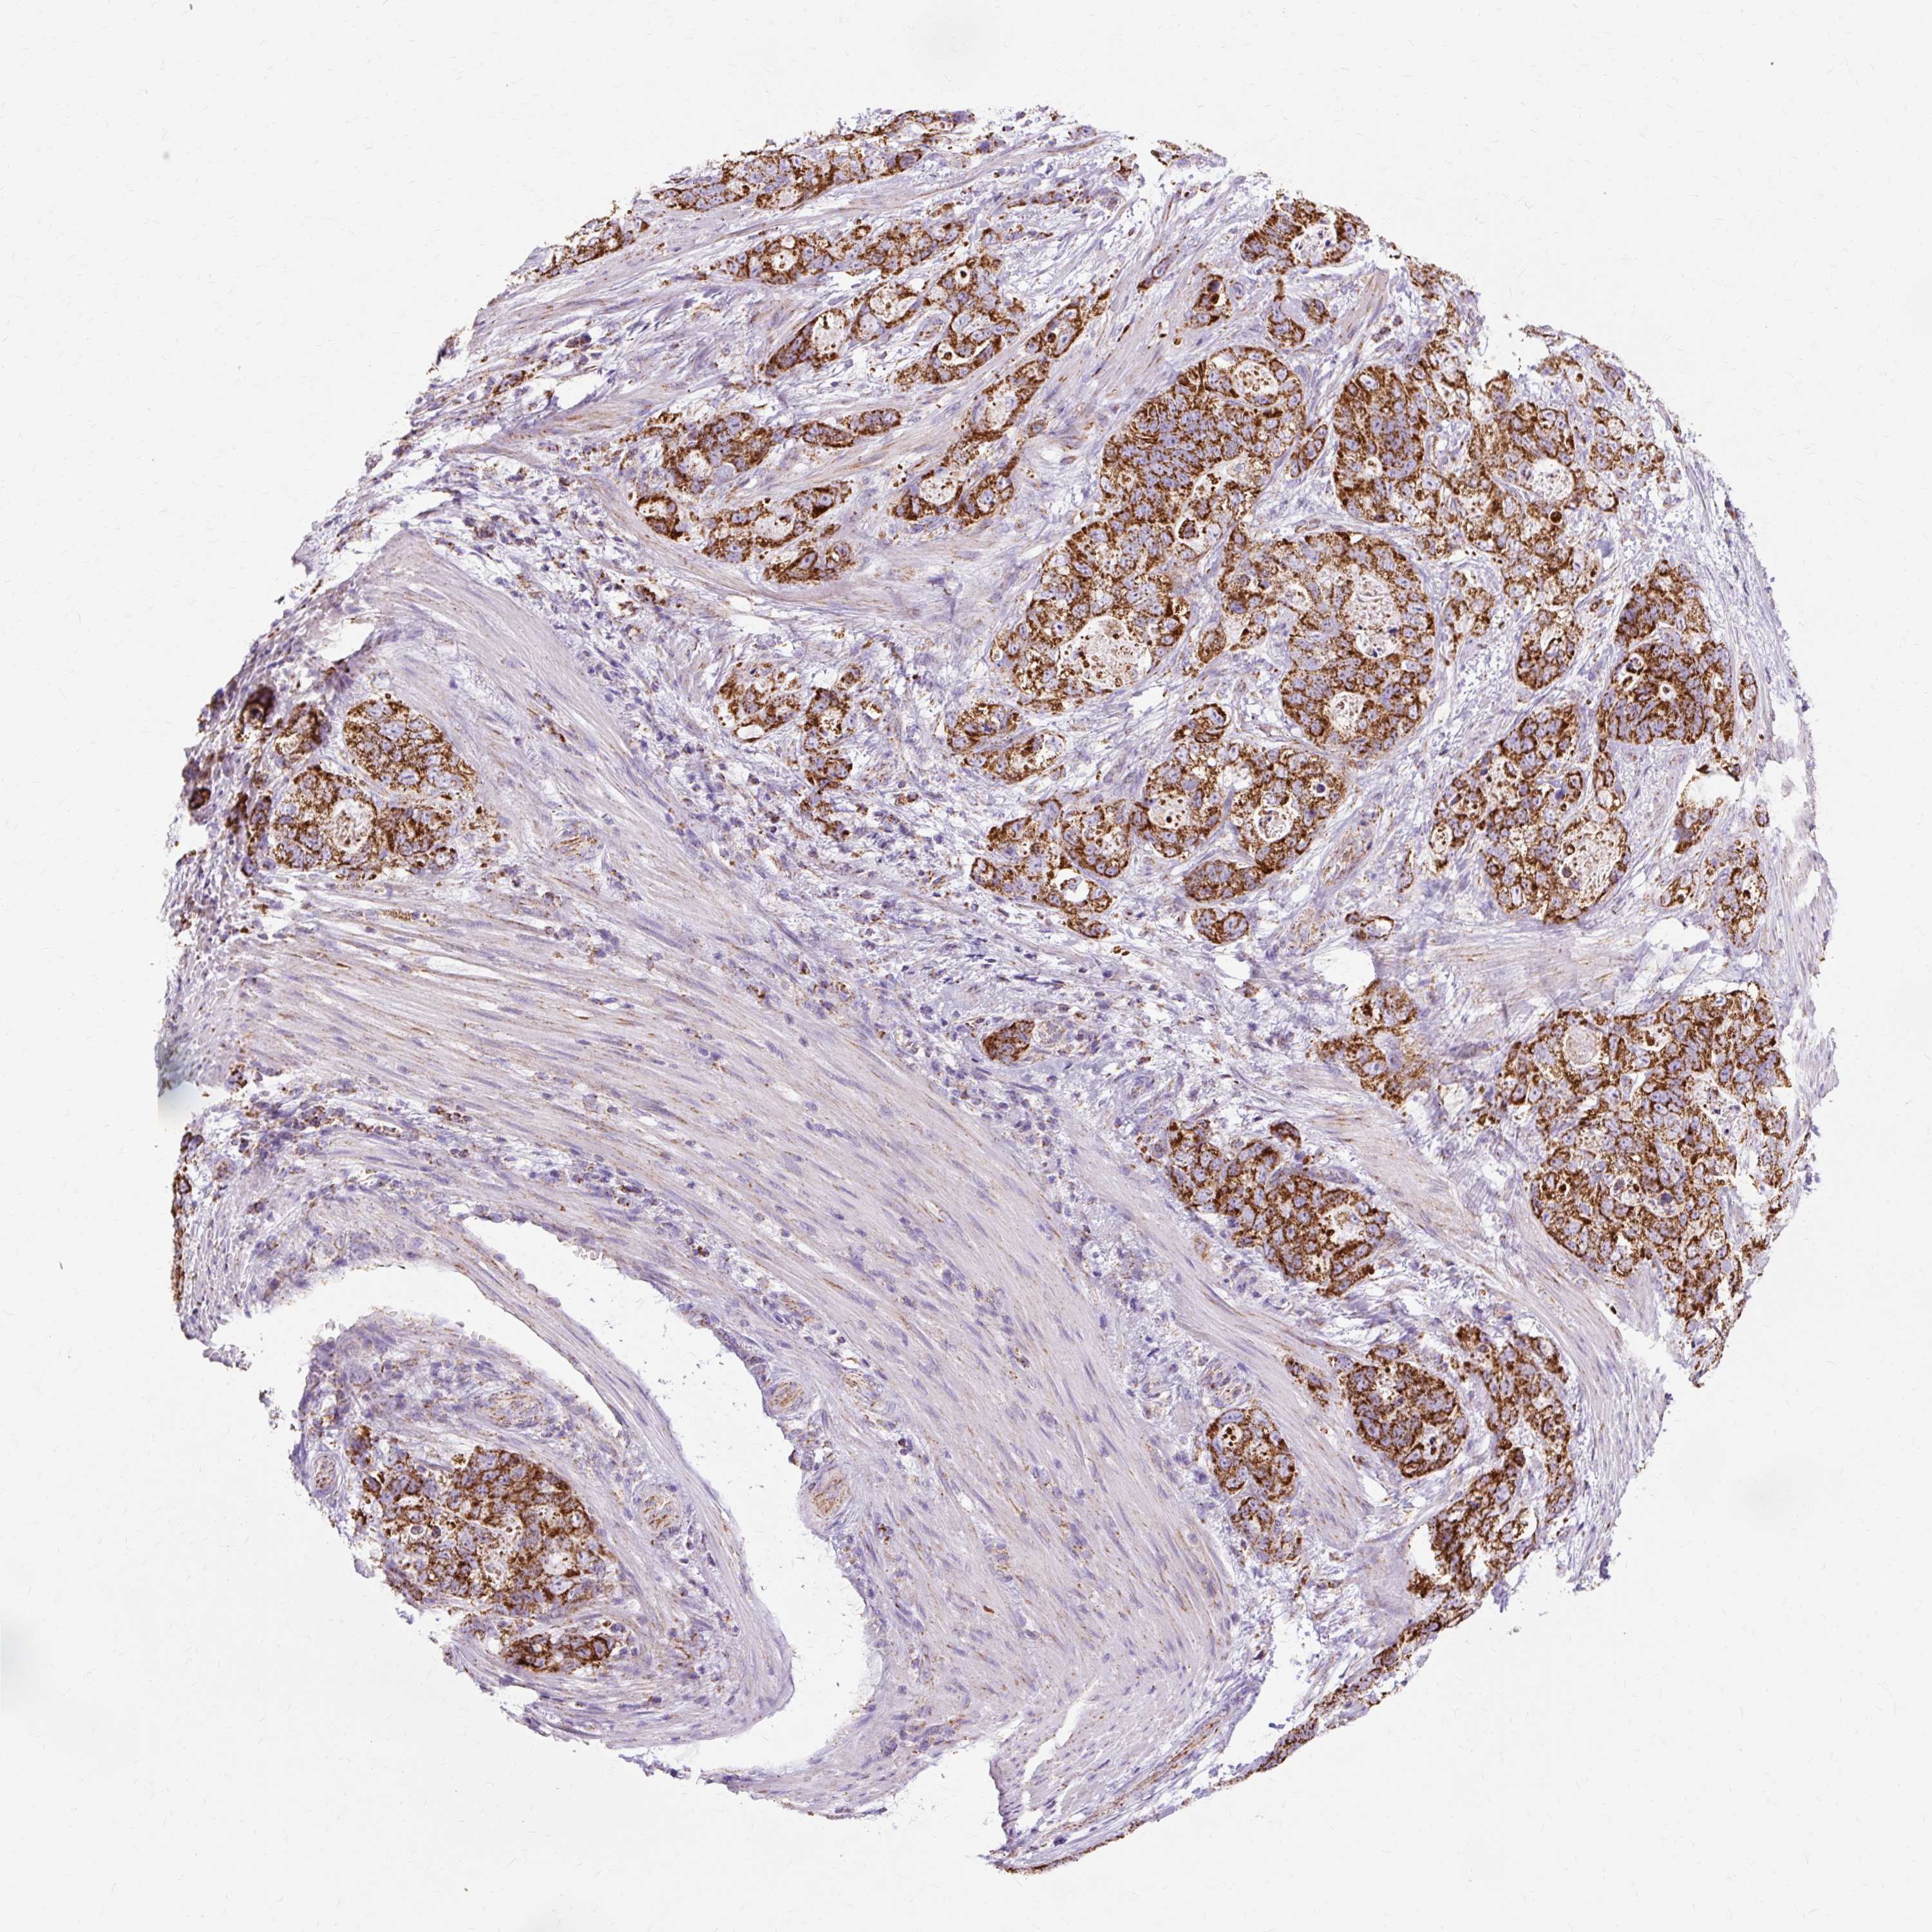

STOMACH CANCER - Protein expressioni

A mouse-over function shows sample information and annotation data. Click on an image to view it in a full screen mode. Samples can be filtered based on level of antibody staining by selecting one or several of the following categories: high, medium, low and not detected. The assay and annotation is described here.

Antibody stainingi

Antibody staining in the annotated cell types in the current human tissue is reported as not detected, low, medium, or high, based on conventional immunohistochemistry profiling in selected tissues. This score is based on the combination of the staining intensity and fraction of stained cells.

Each image is clickable and will lead to virtual microscopy that enables deeper exploration of all samples and also displays staining intensity scores, fraction scores and subcellular localization as well as patient and tissue information for each sample.

Antibody HPA040786

Antibody CAB003782

Staining

High

Medium

Low

Not detected

Intensity

Strong

Moderate

Weak

Negative

Quantity

>75%

75%-25%

<25%

None

Location

Nuclear

Cytoplasmic/membranous

Cytoplasmic/membranous,nuclear

Adenocarcinoma, NOS